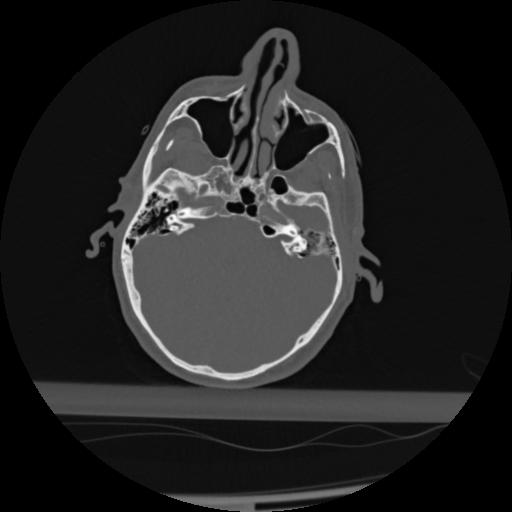

22 ANGIO,CE,Vol,0.5,ANGIO,,